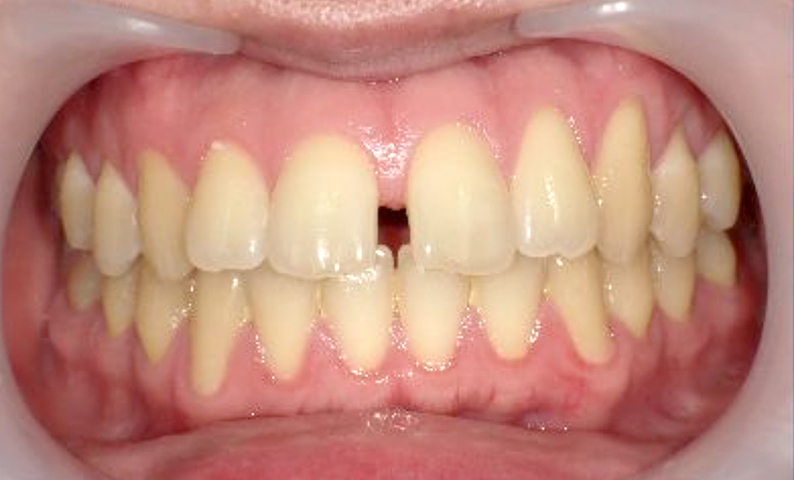

前歯の歯列において、隙間が生じることを一般的に「すきっ歯」といいます。

「すきっ歯(すきっぱ)」は、主に前歯に見られ、目立ちやすく、多くの人がこれを気にしています。

そのため、人前で大きな口を開けて笑うことが抵抗感を生む場合もあります。

| 治療前 | 治療後 |

|---|---|

|